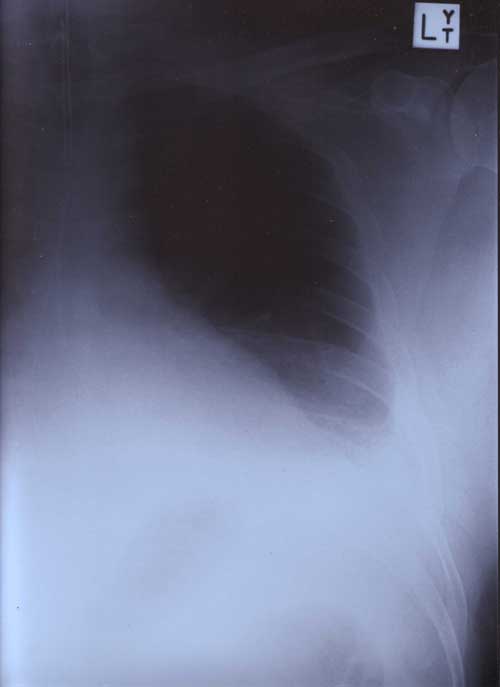

21st January 2000